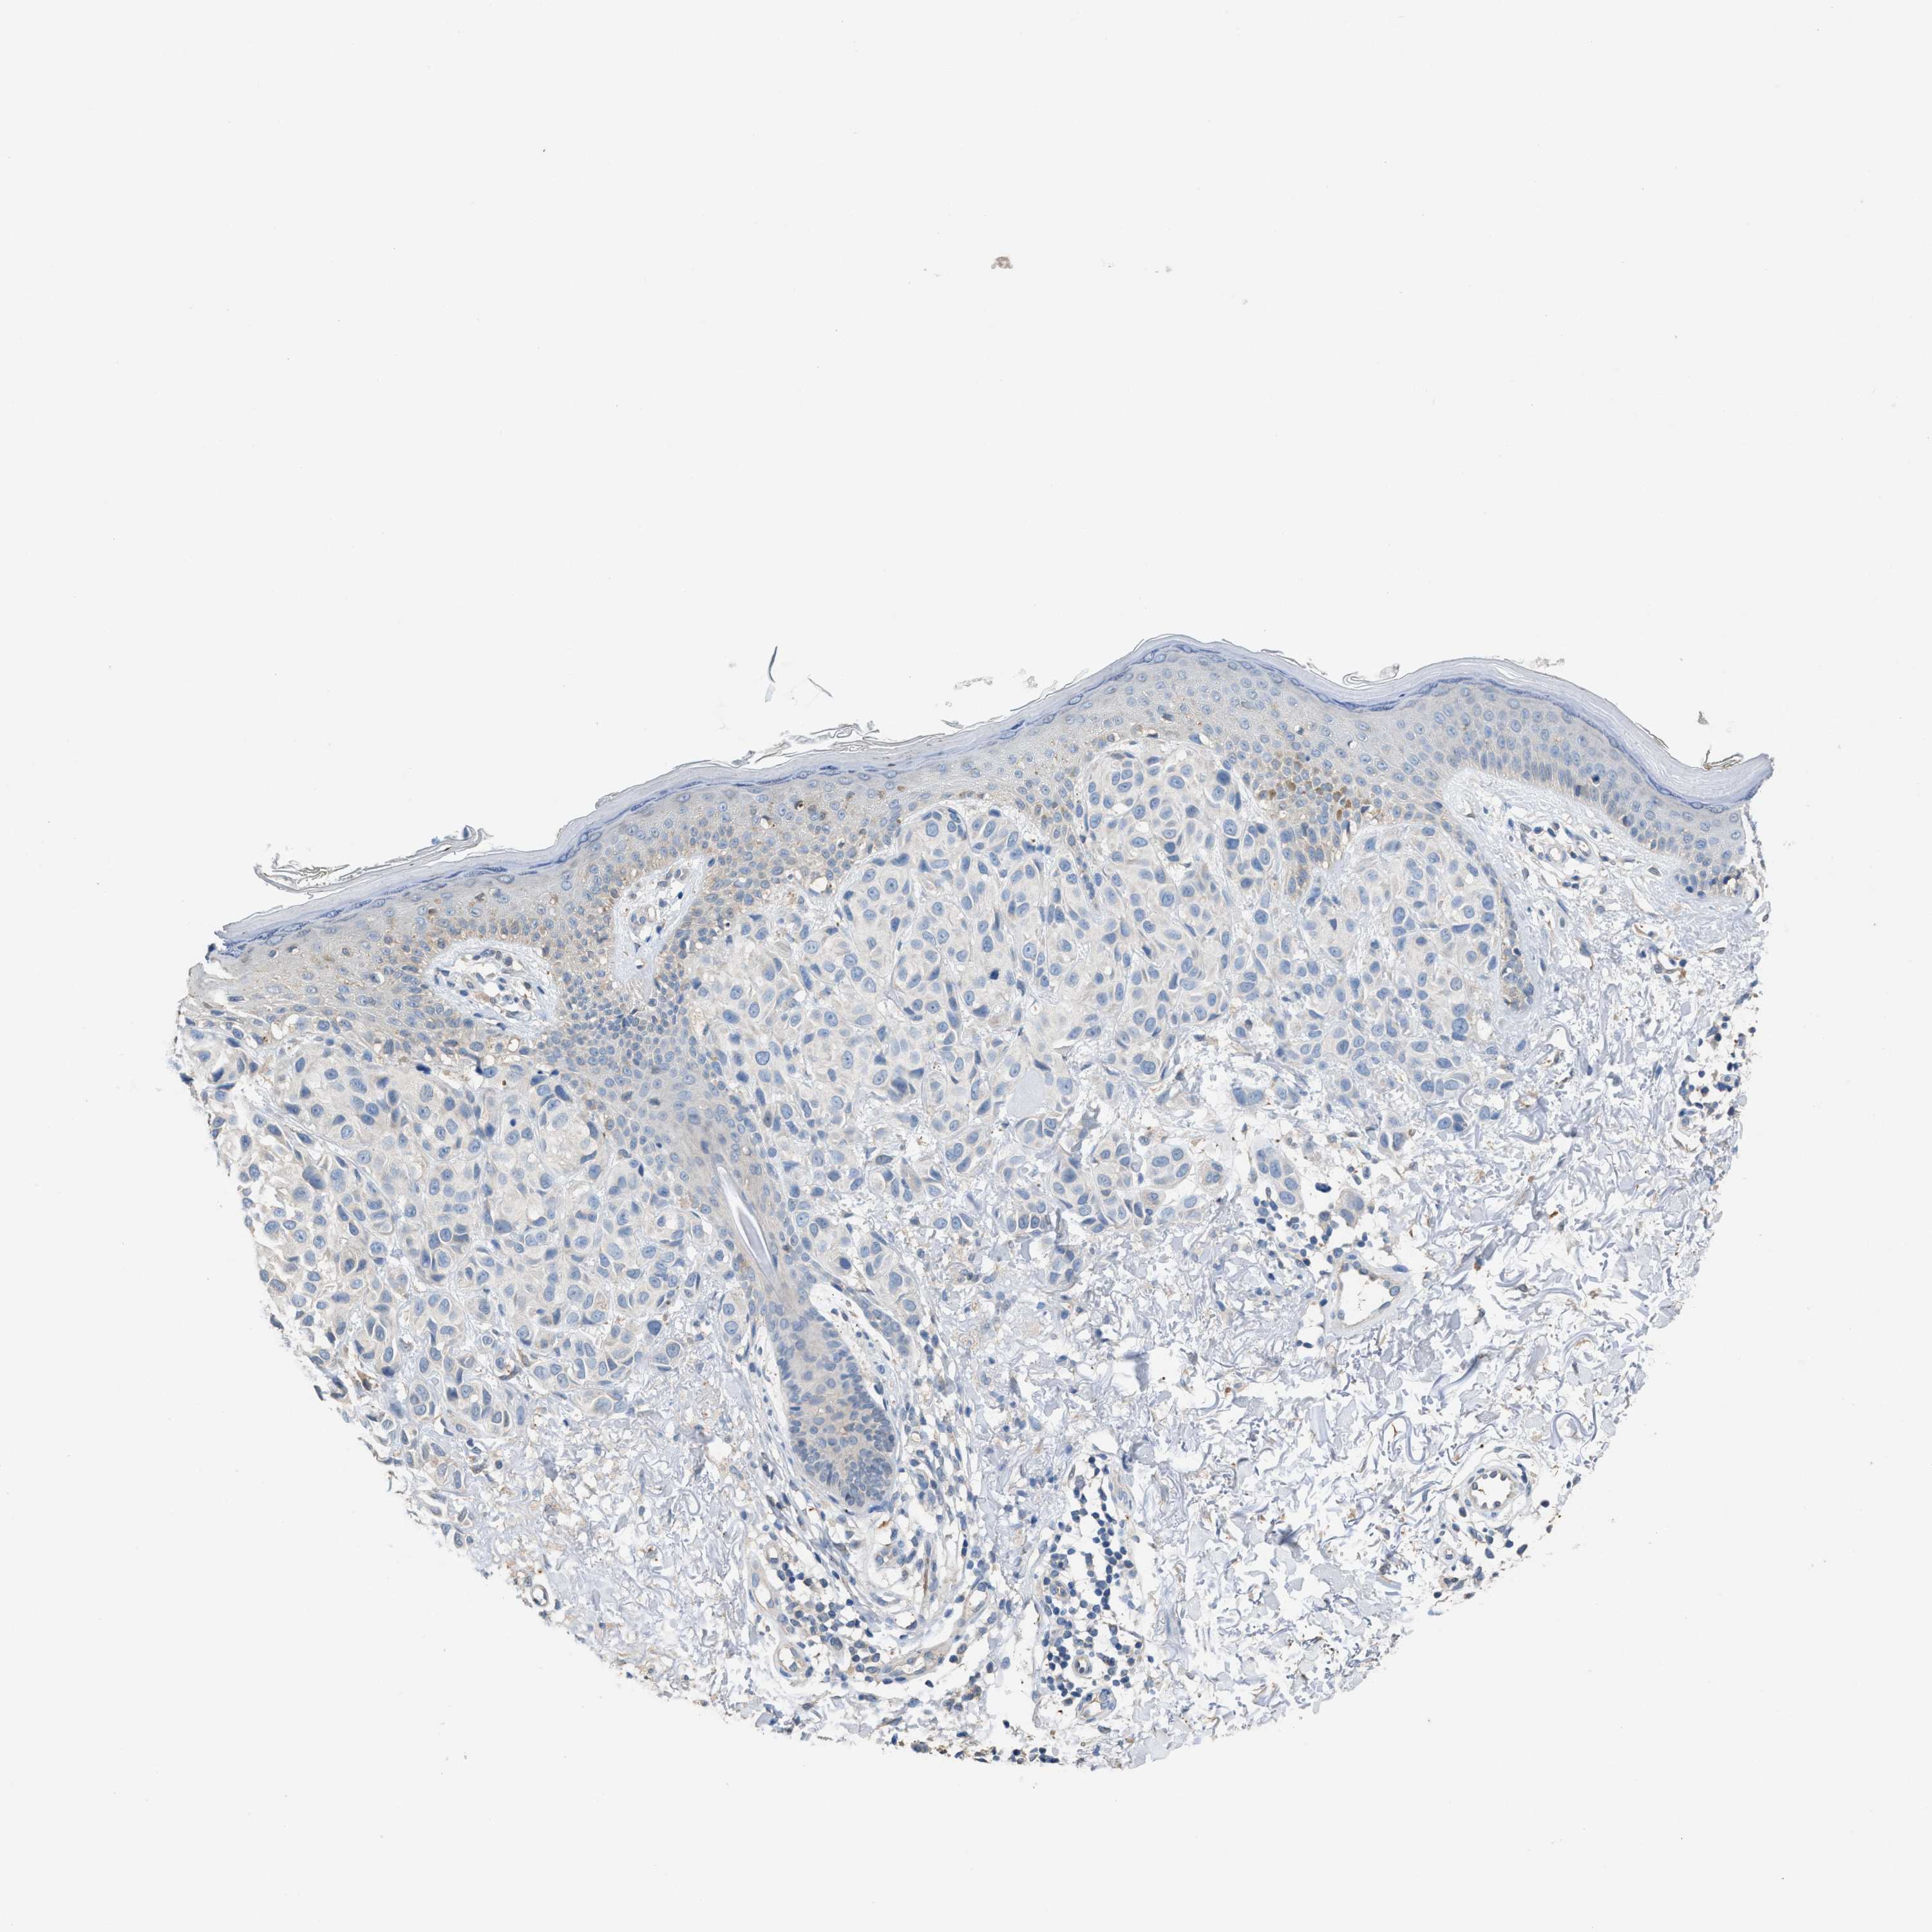

MELANOMA - Protein expressioni

A mouse-over function shows sample information and annotation data. Click on an image to view it in a full screen mode. Samples can be filtered based on level of antibody staining by selecting one or several of the following categories: high, medium, low and not detected. The assay and annotation is described here.

Note that samples used for immunohistochemistry by the Human Protein Atlas do not correspond to samples in the TCGA dataset.

Antibody stainingi

Antibody staining in the annotated cell types in the current human tissue is reported as not detected, low, medium, or high, based on conventional immunohistochemistry profiling in selected tissues. This score is based on the combination of the staining intensity and fraction of stained cells.

Each image is clickable and will lead to virtual microscopy that enables deeper exploration of all samples and also displays staining intensity scores, fraction scores and subcellular localization as well as patient and tissue information for each sample.

Antibody HPA021283

Antibody HPA021332

Staining

High

Medium

Low

Not detected

Intensity

Strong

Moderate

Weak

Negative

Quantity

>75%

75%-25%

<25%

None

Location

Nuclear

Cytoplasmic/membranous

Cytoplasmic/membranous,nuclear

Malignant melanoma, NOS